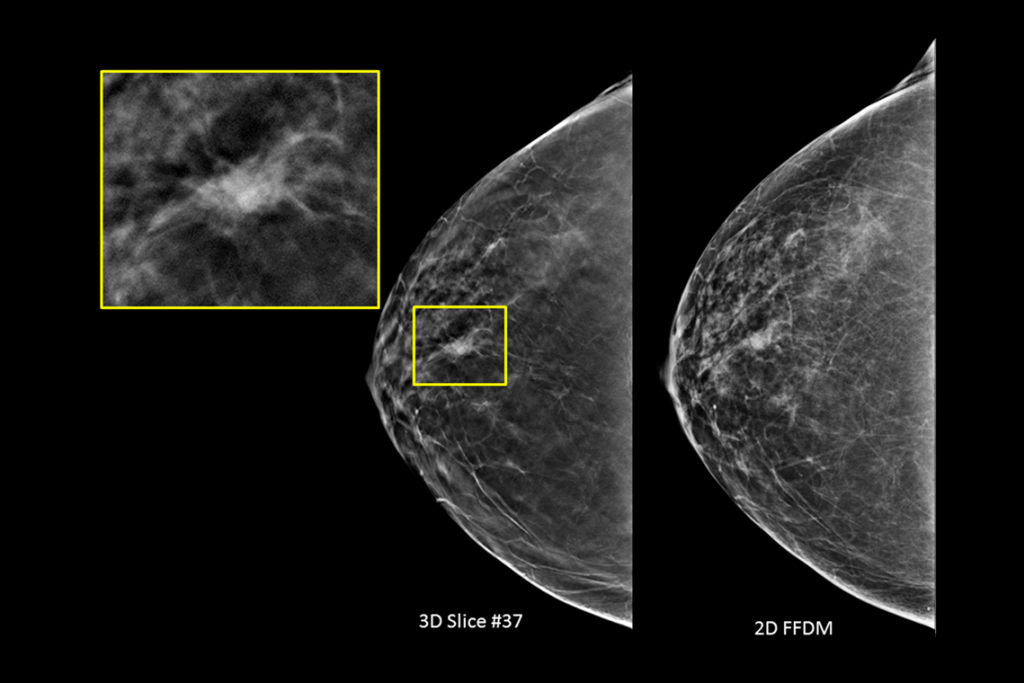

The Selenia Dimensions system delivers proven accuracy of our 3D Mammography exam to detect significantly more invasive breast cancers earlier and reduce call backs vs 2D alone.2-6,*

Detects up to 65% more invasive breast cancer, and reduces recalls by up to 40%, compared to 2D alone.2-4,*

Superior Accuracy

Superior accuracy for women with dense breasts compared to 2D alone.6

Clinical Images